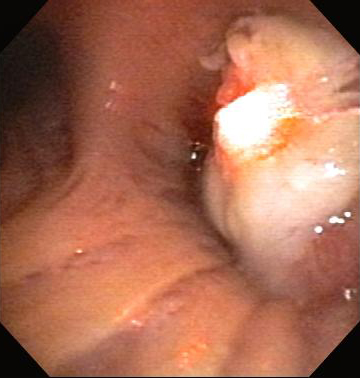

Post-lung transplant anastomotic bronchial stenosis: electrocautery radial incision

From the collections of Jose Fernando Santacruz MD, FCCP, DAABIP and Erik Folch MD, MSc; used with permission